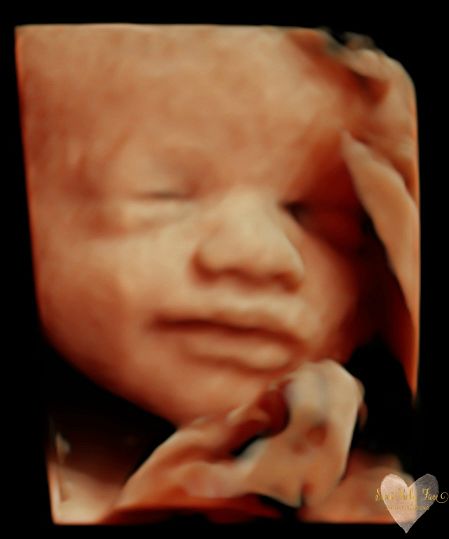

3D/4D/5D Ultrasound Gallery

Take a peek at our Photo Gallery. All of our 2D, 3D, 4D, HD elective ultrasound images are truly ours. They come directly off our machine from our highly trained staff. We can start getting great 3D/4D images as early as 10 weeks!